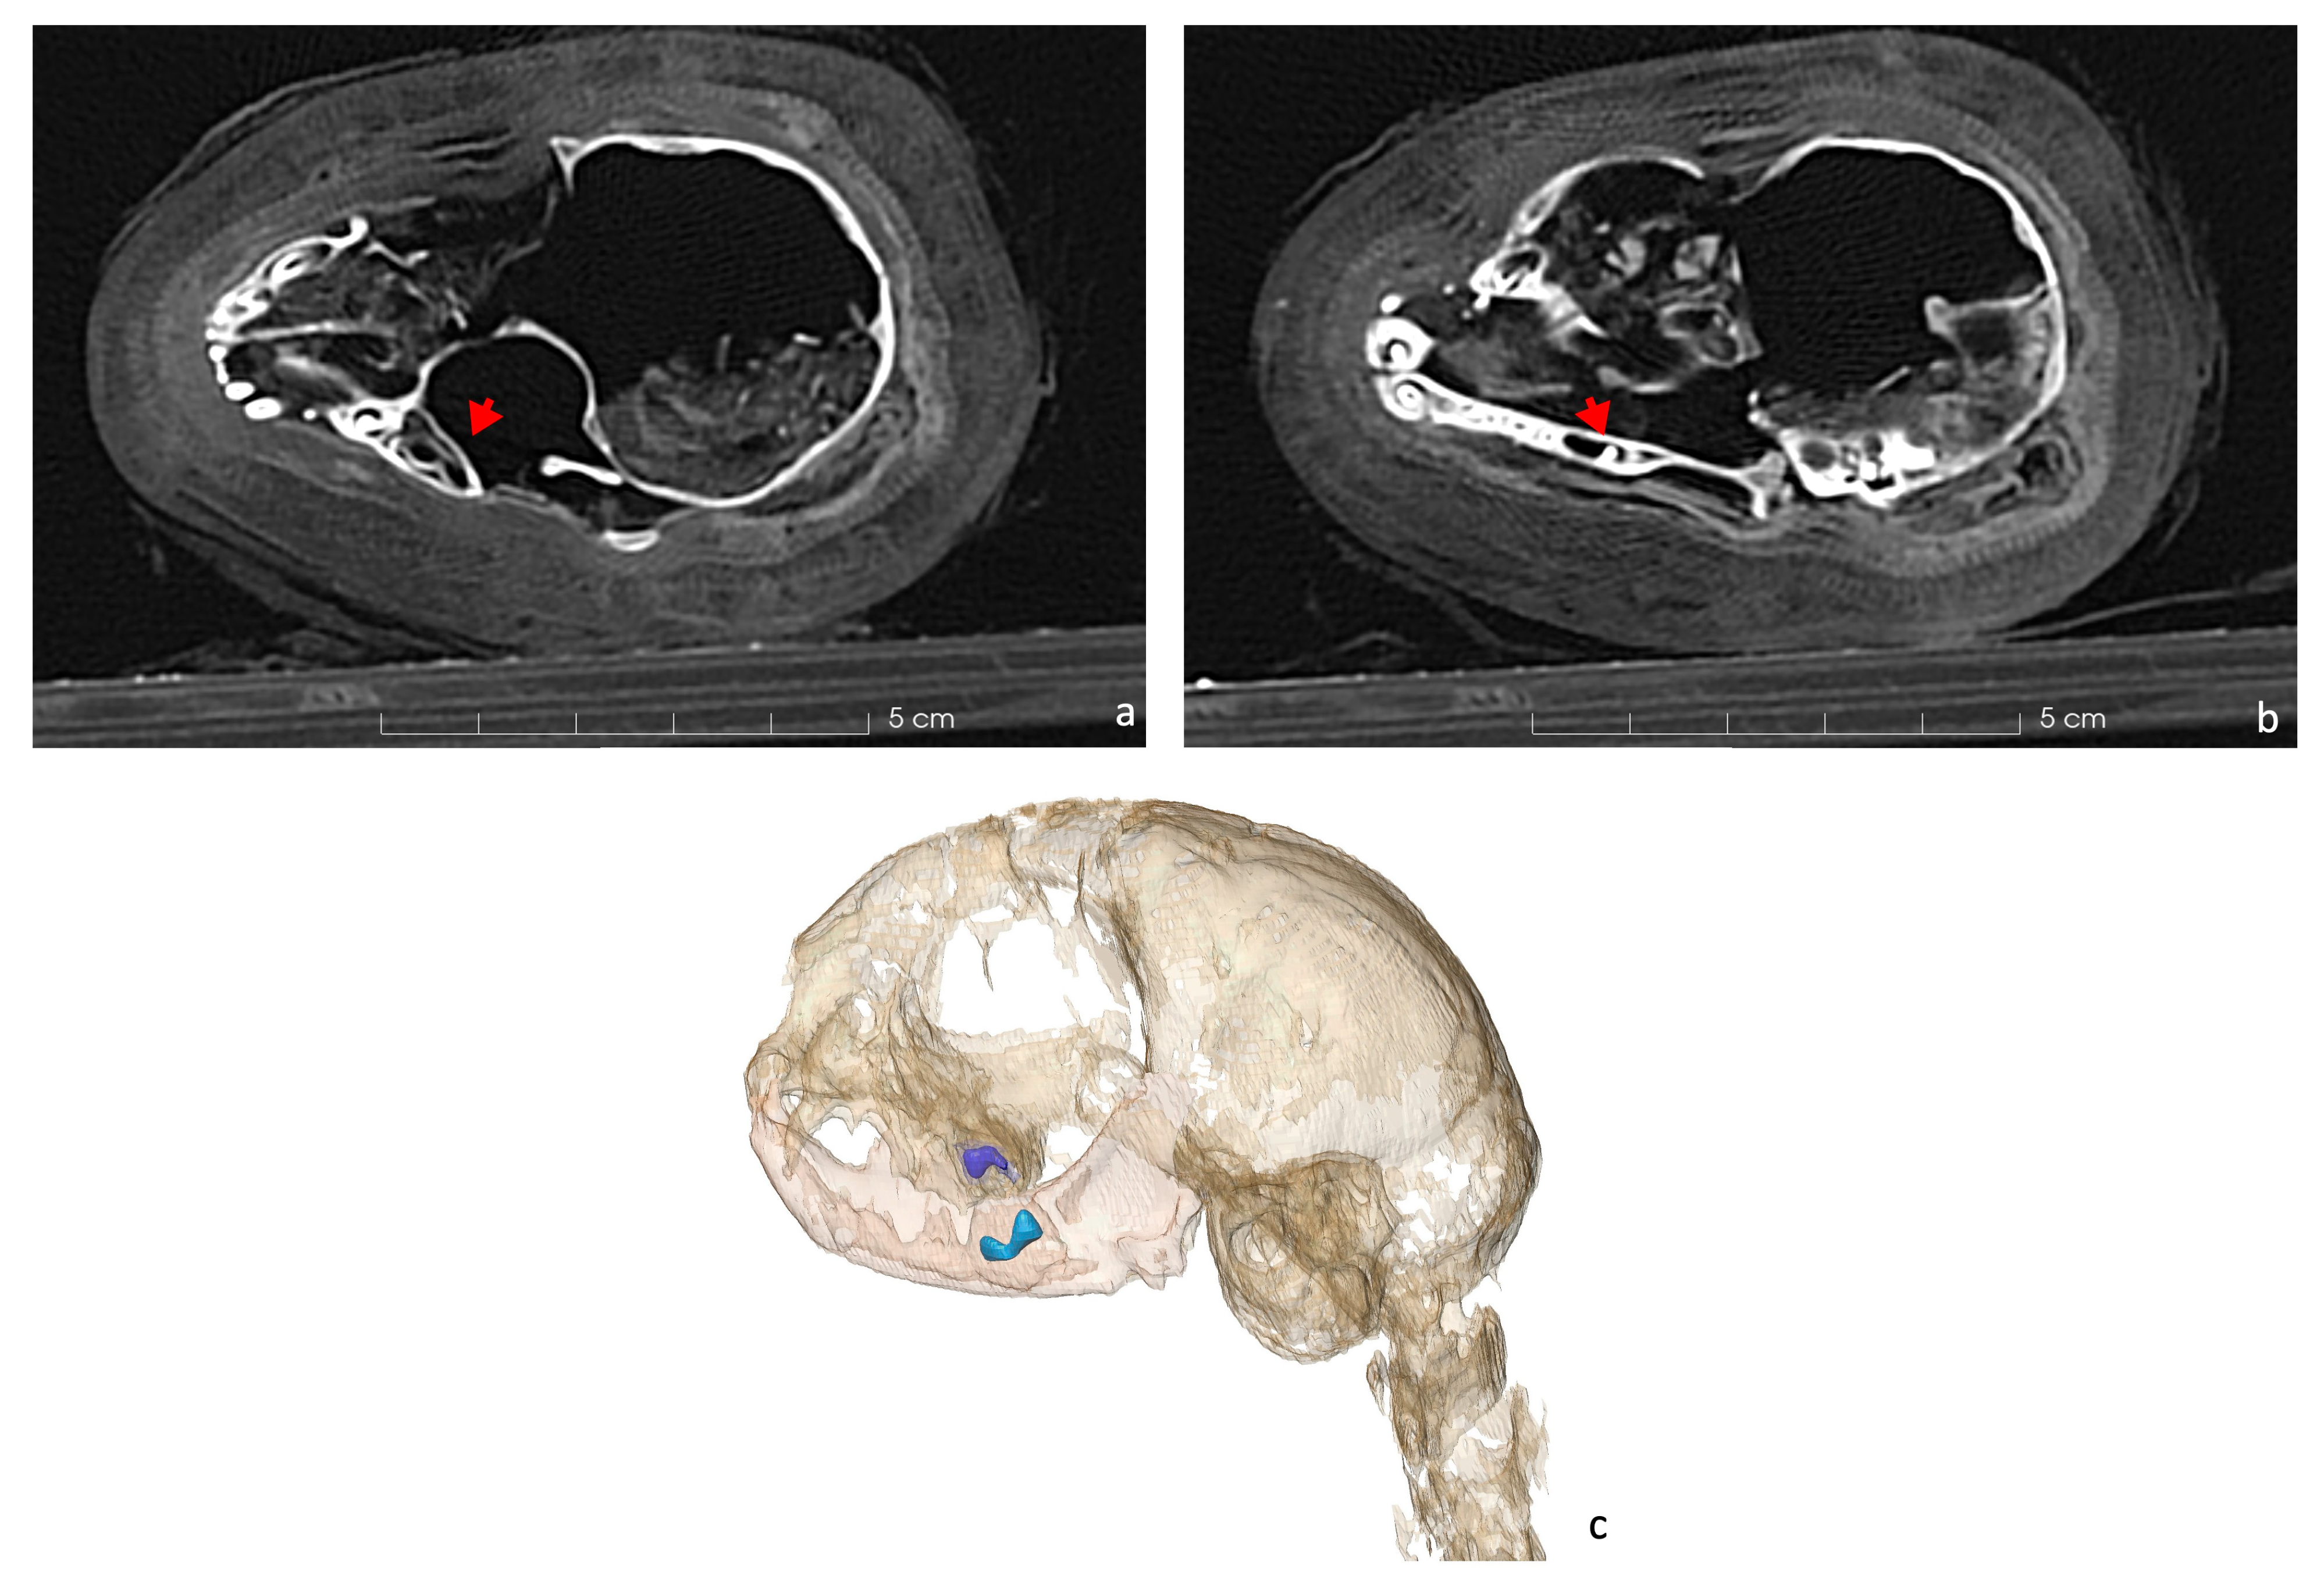

The scans revealed unerupted permanent teeth within both the mandible and maxilla (Figure 3). The canines shown in the figure are deciduous, and the permanent teeth have yet to erupt. In the maxilla, the fourth premolar remains unerupted (Figure 3a), while in the mandible, the first molar is still inside its chamber (Figure 3b). This helps in establishing the age at death.

Figure 3.

Axial CT scan of the cat’s dentition. (a) The unerupted fourth premolar in the maxilla is indicated by a red arrow. (b) The molar in the mandible remains enclosed within its chamber (red arrow). (c) 3D rendering of the skull and mandibles with the gems of the upper fourth premolar (in purple) and lower first molar (in blue) still in the alveoli.

The scans show that the distal epiphyses of the femurs were unfused, as were the proximal epiphyses of the tibiae (Figure 8). Regarding the forelimbs, the proximal epiphyses of the right humerus and the right ulna were unfused, as well as the distal epiphysis of the right radius. All these findings are an indicator of an immature individual [42,43]. The young age is a problem for its taxonomic identification, as the diagnostic skeletal features are not fully developed and biometry is limited to certain skeletal elements. The distal breadth of the humerus (Bd, following von den Driesch, 1979) is 15.8 mm. The humerus was chosen as the distal epiphyses was already fully ossified. Even if a possible slight further growth of the bone cannot be excluded, the size is in line with the variation of Felis silvestris and looks to be too small for the jungle cat Felis chaus [14]. The size overlaps with that of the sand cat Felis margarita [14], but this species is considered to be much rarer and looks to be uncommon in the zooarcheological record in Egypt [16]. If we hypothesize the attribution to Felis silvestris, common amongst votive mummies [47,48], the individual was almost certainly younger than 9 months [43,44]. Furthermore, the dentition was still composed of deciduous teeth, while the permanent molars were unerupted (Figure 3b) and the fourth premolar of the maxilla was still within the chamber (Figure 3a). Since molars erupt at 5 or 6 months, and the eruption of permanent premolars occurs between 4 and 6 months [45], it is possible to hypothesize that the animal was probably less than about 5 months old at death. This age is very common among cat mummies, as other mummies prove [47,48,50].